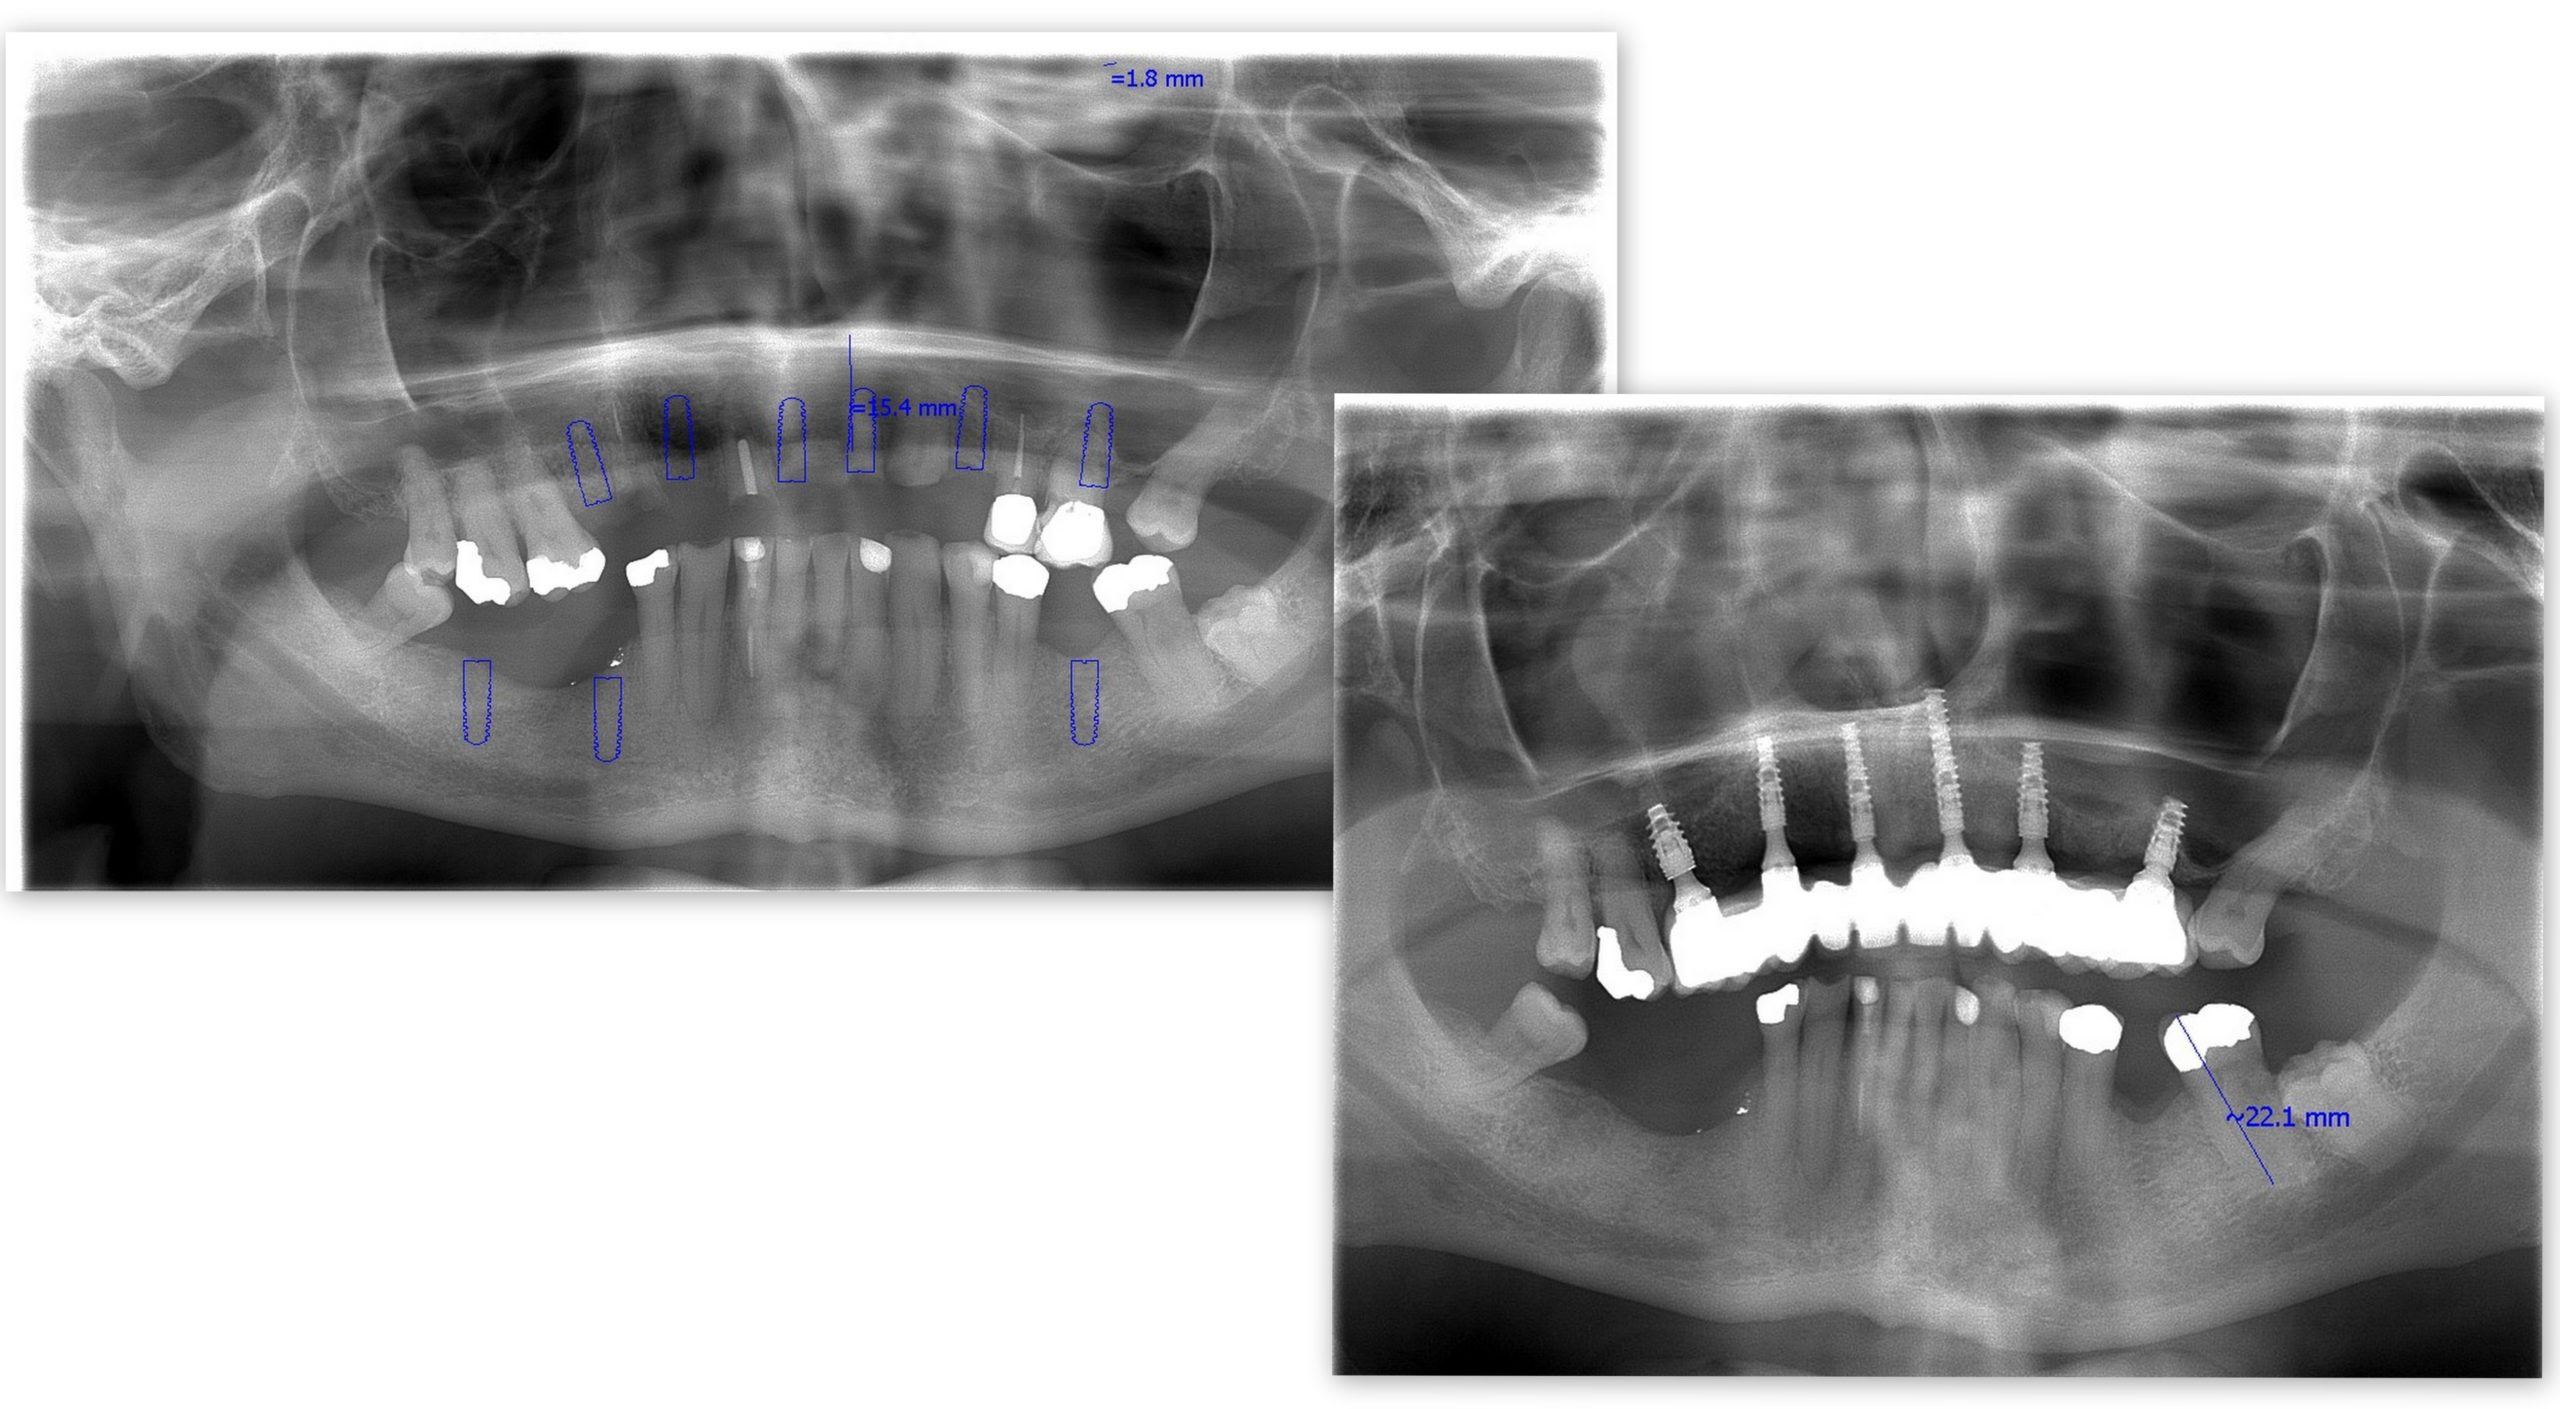

Robert from Scotland decided to travel to Dental Holiday in Slovakia to have dental implants at the age of 76. Dental implants at any age are a good idea!

It might seem daunting at any age to travel across Europe to have dental treatment, yet Robert took the challenge to change his smile. This just goes to show dental implants at any age are a good idea. Robert is so happy with his new smile and is excited to experience what life has in store for him now.